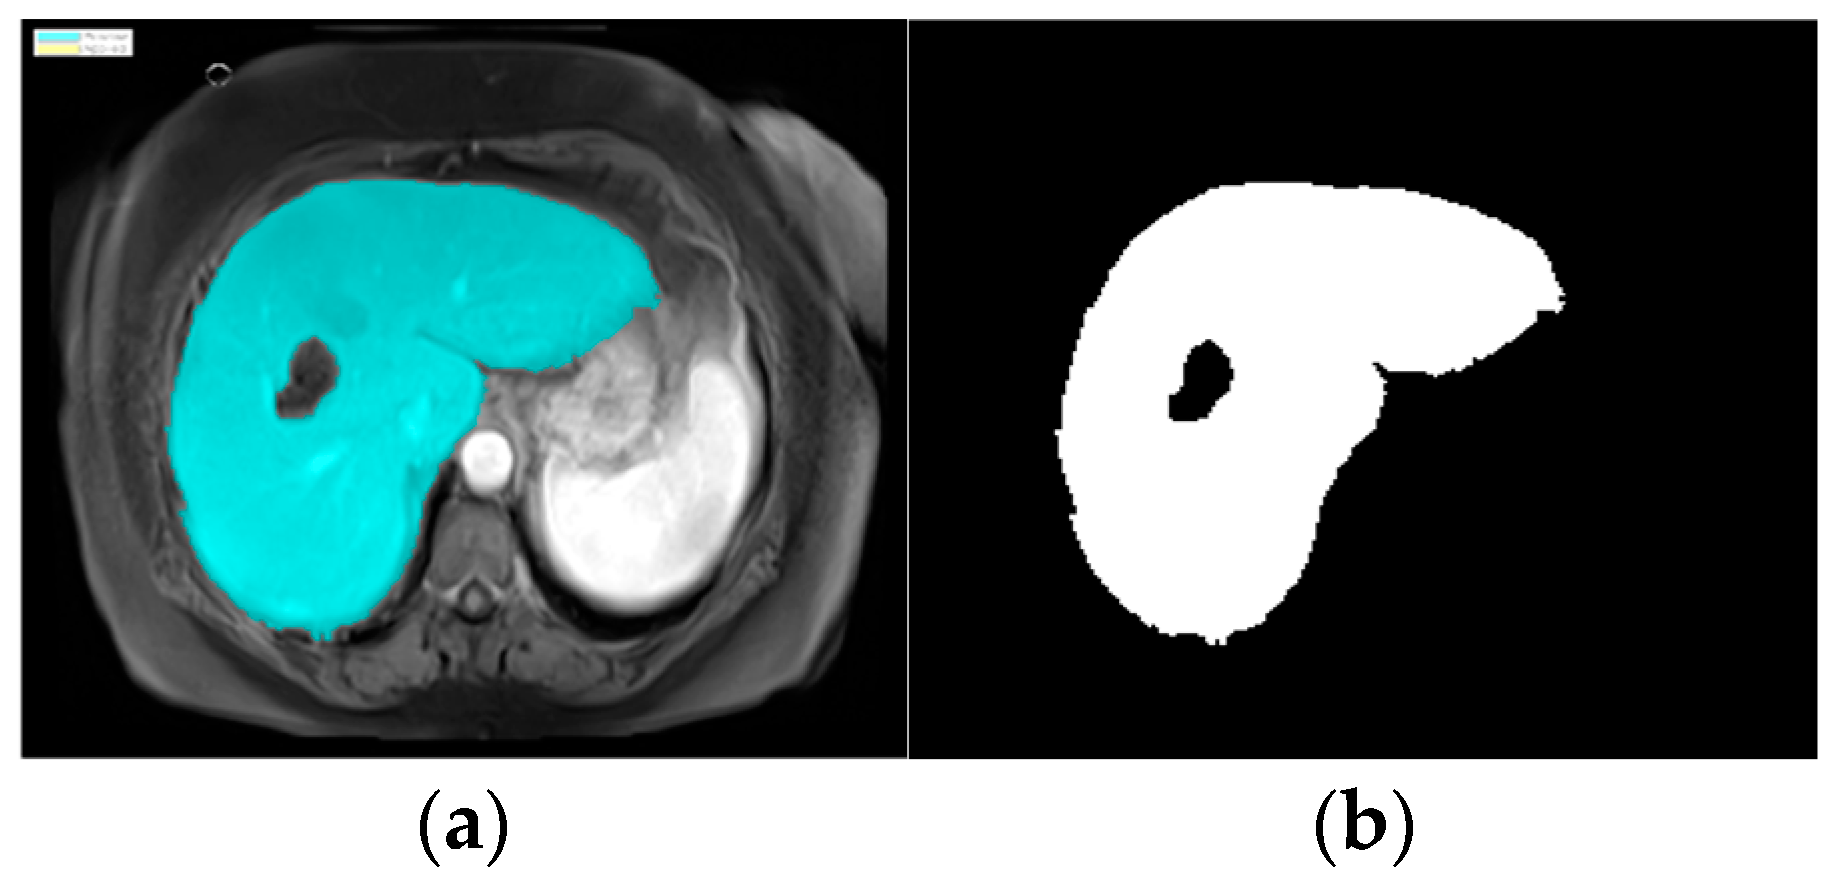

In image segmentation, we highlighted the liver in the image to easily and automatically identify it in CT scans [7]. CT images include many parts of the human body [8], so we used an image segmentation model in MATLAB (version R2024a). The process automatically proceeded to the image segmentation stage, applying the specific region of interest (ROI) function. The K-means clustering technique algorithm was used. The ROI function was used to blur, highlight, and apply a brightness threshold, where pixels with high values were considered a part of the ROIs. After identifying the liver, the image was converted to a binary image, as shown in Figure 4.

The watershed algorithm treats the image as a topographic surface, where pixel intensities represent the height of the surface. It identifies the boundaries of the liver by stimulating the flow of water, filling up the low-intensity regions (background) while keeping the high-intensity regions (liver) separate. After applying the watershed, the identified liver region was converted to a binary image, as shown in Figure 5. This segmentation process made it easier to locate the liver and subsequently focuses on detecting any abnormalities or tumors.

Following the application of the watershed algorithm, we successfully segmented the liver region and converted it into a binary image (Figure 4), facilitating precise tumor detection and recognition shown in Figure 5. The implementation of 8-connectivity during segmentation further ensured the accurate identification of multiple tumors, including those with complex shapes. This approach enables the effective differentiation of tumors from surrounding tissues, leading to reliable tumor size estimations.

Figure 4. Images of parts of liver and tumors in liver: (a) ROI masking and (b) liver structure in binary code.